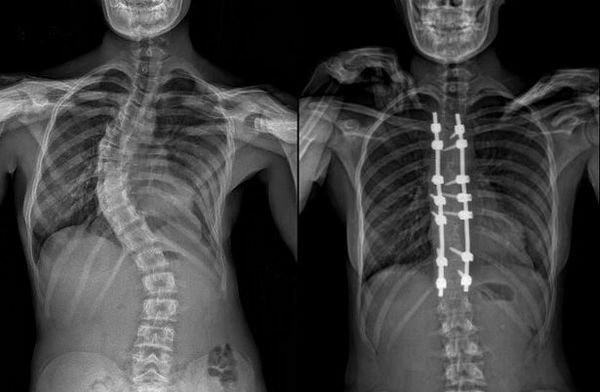

Сколиоз - это сложное искривление позвоночника в плоскостях фронтальной и сагиттальной, сопровождающееся скручиванием позвонков.

При развитии сколиоза на ранних стадиях возникает только боковое искривление, но по мере усиления деформации также происходит искривление позвоночника в сагиттальной плоскости и увеличивается скручивание вокруг вертикальной оси (в горизонтальной плоскости).